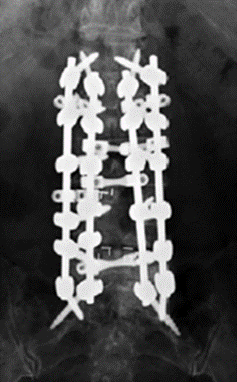

T10骨盆固定,出现交界性后凸

行翻修手术:T9/10SP截骨,延长到T4固定,预防性双侧肋骨固定(VEPTR)

图32-33 肋骨固定